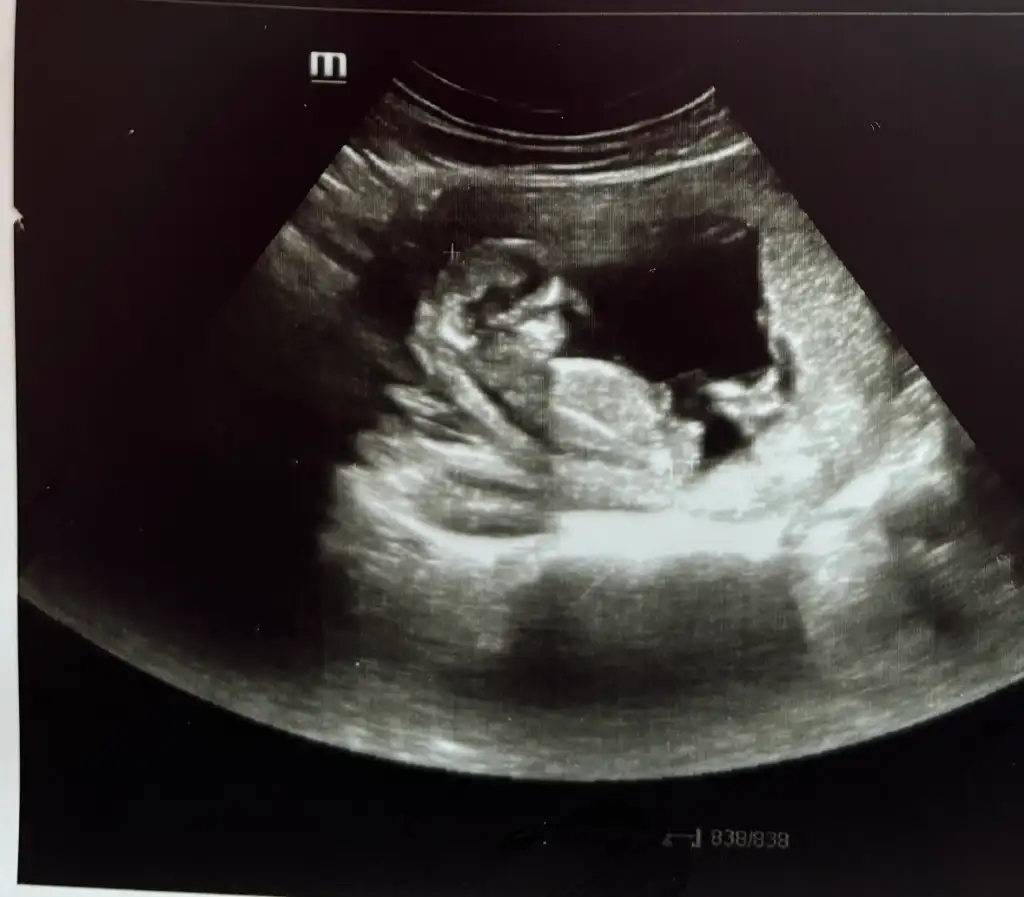

Ay rica etsem banada bakar mısınız 12+1 ultrason resmi vermedi doktor videodan ekran görüntüsü aldım